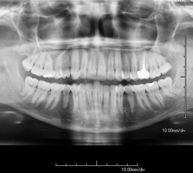

- RX Ortopantomografía (RX Panorámica dental)

Técnica mediante la cual, utilizando rayos X, se obtienen imágenes de ambos maxilares y de las piezas dentarias para su estudio. Indicaciones: piezas dentales retenidas, estudio de ortodoncia, estudio de implantes dentales.